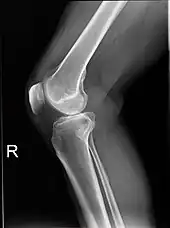

Projectional radiographs

Projectional radiography is the practice of producing two-dimensional images using X-ray radiation. Bones contain a high concentration of calcium, which, due to its relatively high atomic number, absorbs X-rays efficiently. This reduces the amount of X-rays reaching the detector in the shadow of the bones, making them clearly visible on the radiograph. The lungs and trapped gas also show up clearly because of lower absorption compared to tissue, while differences between tissue types are harder to see.[101]

Projectional radiographs are useful in the detection of pathology of the skeletal system as well as for detecting some disease processes in soft tissue. Some notable examples are the very common chest X-ray, which can be used to identify lung diseases such as pneumonia, lung cancer, or pulmonary edema, and the abdominal x-ray, which can detect bowel (or intestinal) obstruction, free air (from visceral perforations), and free fluid (in ascites). X-rays may also be used to detect pathology such as gallstones (which are rarely radiopaque) or kidney stones which are often (but not always) visible. Traditional plain X-rays are less useful in the imaging of soft tissues such as the brain or muscle. One area where projectional radiographs are used extensively is in evaluating how an orthopedic implant, such as a knee, hip or shoulder replacement, is situated in the body with respect to the surrounding bone. This can be assessed in two dimensions from plain radiographs, or it can be assessed in three dimensions if a technique called '2D to 3D registration' is used. This technique purportedly negates projection errors associated with evaluating implant position from plain radiographs.[102]